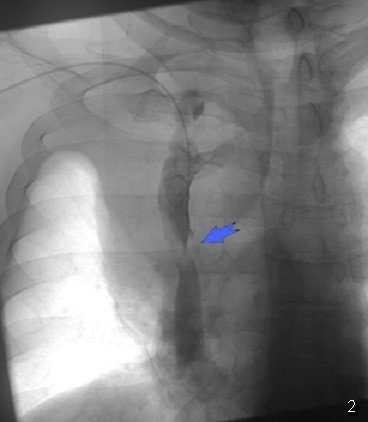

Sepsisli xəstələrdə rentgenoloji müayinədə mediastinumda hava görünməsi yüksək şübhə əlamətidir (Şəkil 9).

Şəkil 9. Mediastinal emfizema